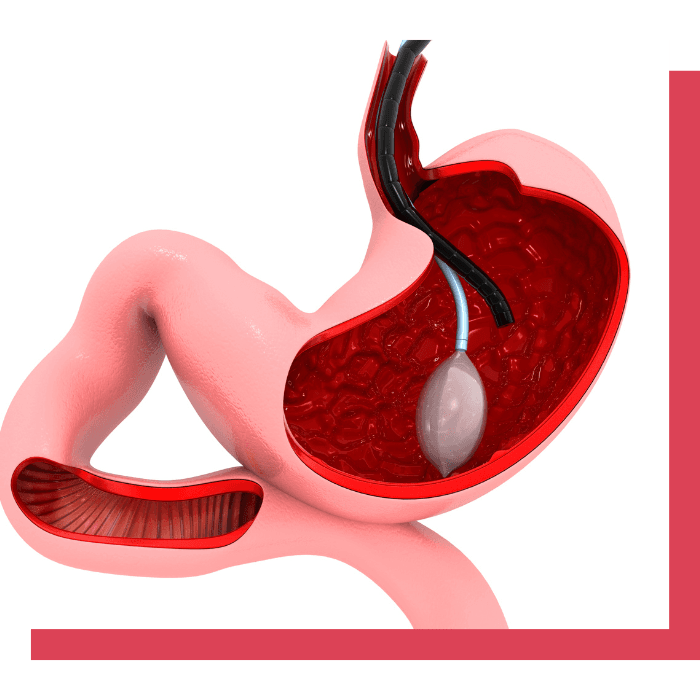

تُعد عملية بالون المعدة واحدة من الحلول الفعّالة التي تساعد الأشخاص في التخلص من الوزن الزائد دون الحاجة إلى تدخل جراحي. تهدف هذه العملية إلى تقليل حجم المعدة بشكل مؤقت من خلال إدخال بالون طبي، مما يعزز الشعور بالشبع ويساهم في تقليل كمية الطعام المتناولة. في هذه الصفحة، سنتعرف على تفاصيل عملية بالون المعدة، كيف تتم، فوائدها، نصائح ما بعد العملية، بالإضافة إلى الإجابة على بعض الأسئلة الشائعة التي قد تكون لديك.

تعتبر عملية بالون المعدة واحدة من الحلول المبتكرة للتخسيس التي لا تتطلب جراحة، مما يجعلها خيارًا مثاليًا للأشخاص الذين يرغبون في فقدان الوزن بشكل آمن وفعّال دون اللجوء إلى العمليات الجراحية. يتم خلالها إدخال بالون طبي إلى المعدة باستخدام المنظار، حيث يُملأ بالهواء أو السائل لتقليص المساحة المتاحة للطعام وبالتالي الحد من كمية الطعام المتناولة.

عملية بالون المعدة هي إجراء غير جراحي يتم تحت تأثير التخدير الموضعي أو التهدئة. يتم إدخال بالون صغير عبر الفم إلى المعدة باستخدام المنظار الطبي.